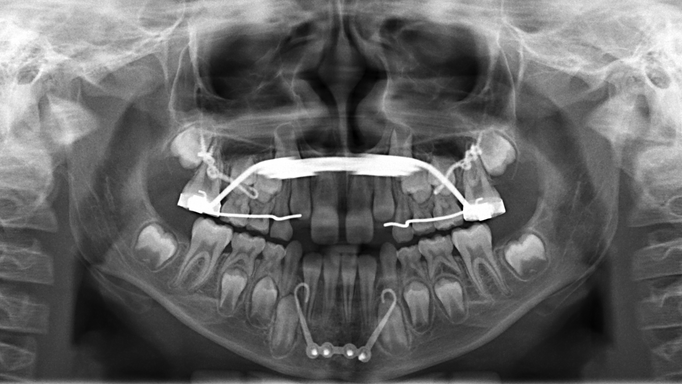

Operationsplanung

Die Planung des Eingriffs erfolgt an unserer Klinik durch eine dreidimensionale Simulation der Bewegungen der zahntragenden Anteile der Kiefer anhand einer zuvor angefertigten DVT (digitale Volumentomografie, modernes 3D-Röntgenverfahren). Die für die Durchführung der Operation erforderlichen Schienen (Splints) können so ebenfalls in optimaler Passung 3D-gedruckt werden.

Alternativ kann die Operation „klassisch“ über Gipsmodelle in einem sogenannten Artikulator geplant werden. Die optimale Kiefer- und Zahnposition wird in der Regel über ein simultanes Verschieben des Ober- und Unterkiefers erreicht (bignathe Umstellungsoperation). In Einzelfällen und bei geringen Fehlstellungen kann ein operatives Verlagern von nur einem Kiefer ausreichend sein, auch als monognathe Umstellungsoperation bezeichnet. Die Dauer des stationären Aufenthaltes sowie die Nachbehandlung sind bei beiden Operationsformen identisch.

Je nach Ausmaß der Fehllage kann der Oberkiefer als Ganzes oder in Teilen bewegt werden. Über einen Zugang vom Mund wird die Mundschleimhaut über den Zähnen durchtrennt und der Kiefer mit dünnen Sägeschnitten gelöst. Die Einstellung der gewünschten Unterkieferposition und Verzahnung geschieht mit dem im Vorfeld hergestellten Splint. Nach der Verlagerung wird der Kiefer in der gewünschten Position durch Miniplatten aus Titan fixiert.

Ziel der Operation ist es, den zahntragenden Unterkieferkörper in die gewünschte Richtung zu verlagern und gleichzeitig die ursprüngliche Position beider Kiefergelenke beizubehalten.

Hierzu wird eine stufenförmige Schnittführung im Knochen gewählt. Nach Verlagerung des Unterkieferkörpers besteht so eine große Knochenanlagerungsfläche. Dies trägt zur raschen Knochenheilung und maximalen Stabilität des Operationsergebnisses bei. Die Einstellung der gewünschten Unterkieferposition und Verzahnung geschieht mit dem im Vorfeld hergestellten Splint. Nach der Verlagerung wird der Kiefer in der gewünschten Position durch Miniplatten aus Titan fixiert.